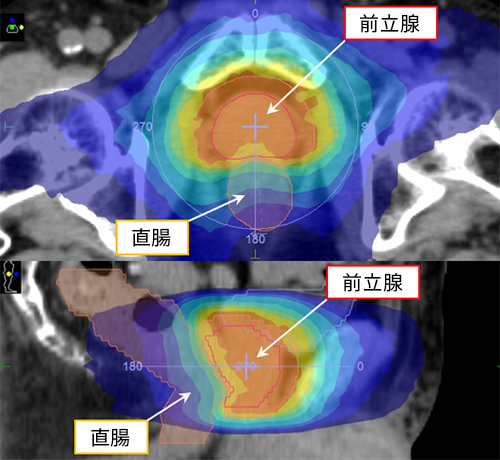

強度変調放射線治療 (IMRT)

病巣に高い放射線量を集中させ、従来の治療法と比較して周囲の正常組織への影響を抑えることが可能な治療法です。

画像誘導放射線治療 (IGRT)

照射の直前や照射中に得られる患者さんの画像情報(X線画像等)を基に日々の放射線治療時の位置誤差を補正しながら正確に治療する技術です。